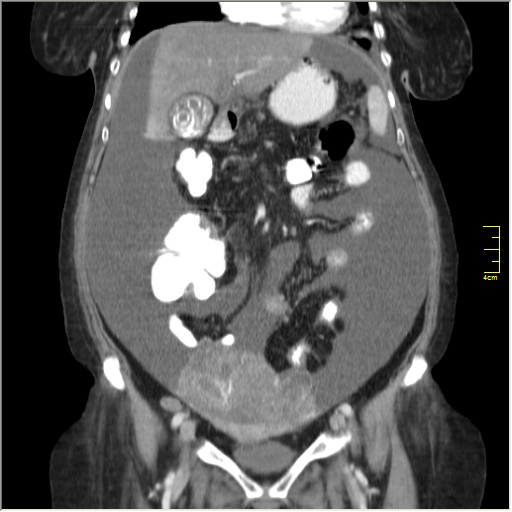

Женщина 72 года. Поступила с жалобами на вздутие живота. После осмотра хирургом, была сразу направлена на КТ брюшной полости.

Итак, асцит с объёмным образованием таза. В данном случае можно быть более конкретным, у пациентки неоплазия правого яичника с региональной лимфаденопатией (увидели?) и выраженным асцитом, характерным именно для злокачественных опухолей яичников. Пациентка оперирована ( операция Вертгейма); диагноз верифицирован: аденокарцинома правого яичника (серозная). Направлена к онкологу для дальнейшего лечения.